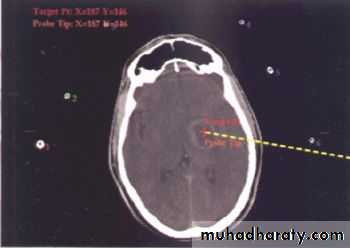

Stereotactic Aspiration of Brain Abscess